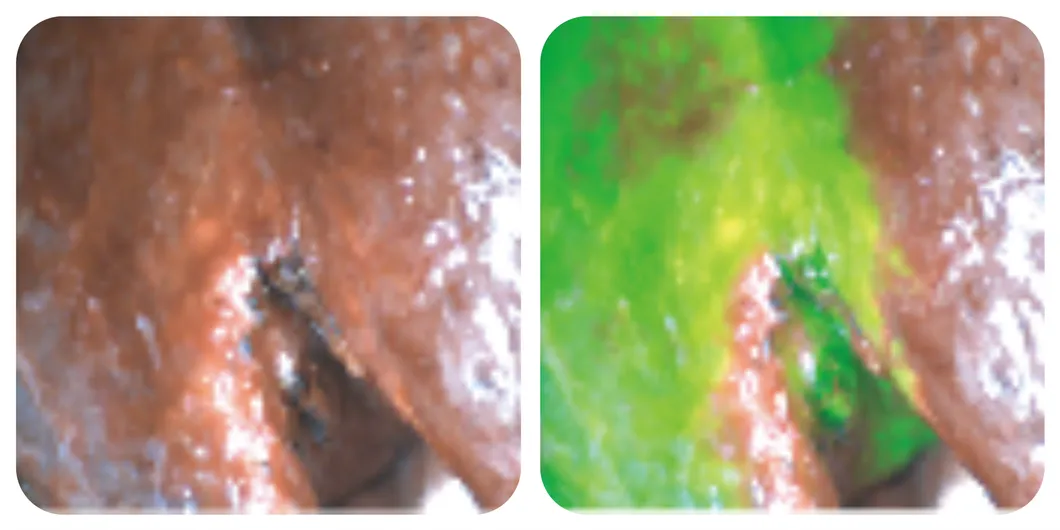

Margin assessment

Liver segment staining

Margin determination